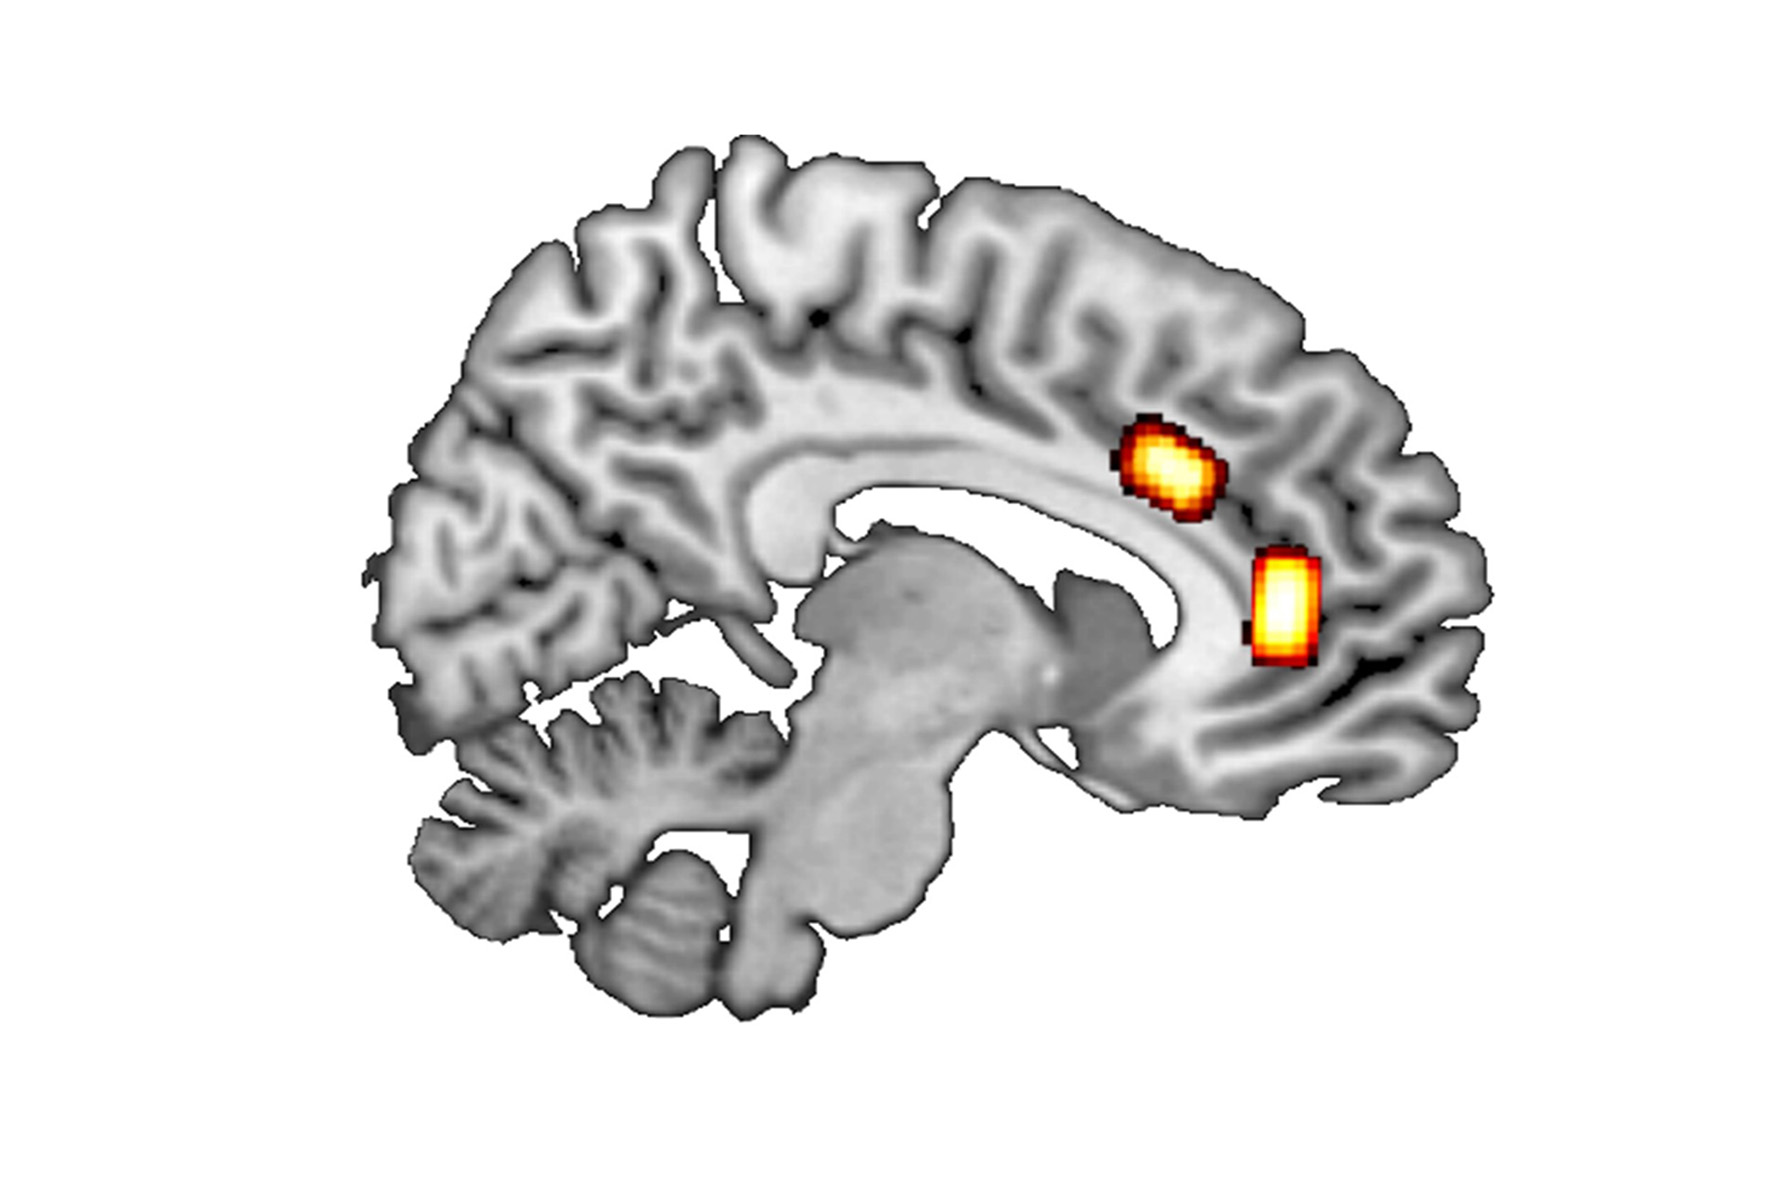

Zum einen betrachteten sie ‚belohnungsbasierte Entscheidungen‘, also solche, bei denen zwischen zwei aktuell vorliegenden Optionen diejenige gewählt wird, die die höchste Belohnung verspricht. Luca Kaiser nennt ein einfaches Beispiel: „Welchen Cappuccino kaufe ich auf dem Weg zur Arbeit, abhängig von dessen Preis, Qualität und Umweg zum Café?“ Frühere Ergebnisse legen nahe, dass solche Entscheidungsprozesse im Gehirn vor allem im ventromedialen Präfrontalkortex (vmPFC) verarbeitet werden.

Bei ‚Patch-leaving-Entscheidungen‘ geht es um langfristige, strategische Fragen, die eine umfangreiche Kosten-Nutzen-Abwägung beinhalten. Beispielsweise, ob man wegen eines Jobangebots von Düsseldorf nach München ziehen soll. Prof. Jocham: „In München locken eventuell ein höheres Gehalt und spannendere Aufgaben, dem gegenüber stehen Stress und Aufwand bei Wohnungssuche und Umzug nach München, höhere Mieten und der Verlust von sozialen Kontakten in Düsseldorf.“ Viele Faktoren beeinflussen also diese Entscheidungsform, die – so die Literatur – im Gehirn im dorsalen anterioren zingulären Kortex, kurz dACC, getroffen werden.

Zentralen Einfluss haben die beiden Botenstoffe Glutamat und GABA; ihr Verhältnis steht für die sogenannte E/I-Balance zwischen erregender und hemmender Übertragungsaktivität. Bei verschiedenen Probanden maßen die Forscher mittels Magnetresonanzspektroskopie die Konzentrationen von GABA und Glutamat in verschiedenen Hirnregionen.

Mit diesen Daten setzte das Team dann das Verhältnis der beiden Botenstoffe mit dem individuellen Entscheidungsverhalten der Probanden in Beziehung. Beim Patch-leaving-Szenario verließen Probanden mit höherem Verhältnis von GABA zu Glutamat im dACC schneller ein schlechter werdendes Habitat. Dagegen bedurften Personen mit höherer Glutamatkonzentration einer größeren Qualitätsverbesserung, bevor sie entschieden, ihren aktuellen Aufenthaltsort zu verlassen.

Im anderen betrachteten Szenario hatten Probanden mit einer im Verhältnis höheren GABA-Konzentration im vmPFC eine deutlich höhere Entscheidungsgenauigkeit: Sie wählten zuverlässiger die Option mit dem höheren Belohnungswert.